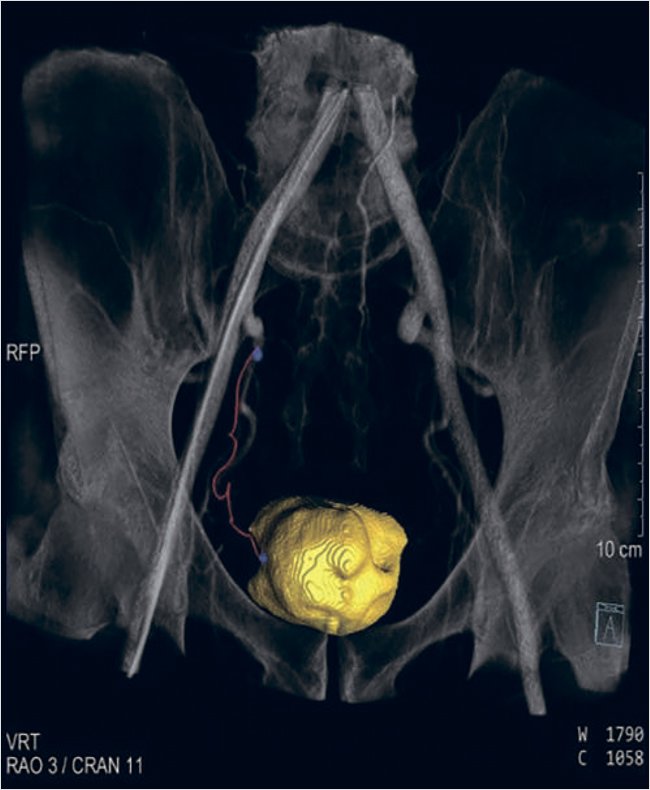

Процедура рентгенэндоваскулярной эмболизации простатических артерий была выполнена на ангиографическом комплексе Siemens Artis Q с программным обеспечением syngo X Workplace VD10 и возможностью проведения ротационной 3D-ангиографии с синхронизацией инъекционной системы для введения контраста. Ангиографические изображения были оценены на предмет верификации артерий таза, простатических артерий и выбора оптимальной проекции для селективной катетеризации простатических артерий при проведения ротационной 3D-ангиографии. Доступ осуществлялся через правую лучевую артерию через интродьюсер 16 см 5F. По диагностическому проводнику 0,035 позиционировался диагностический катетер Pigtail 5F над бифуркацией устьев обеих общих подвздошных артерий. С помощью ангиографического протокола 6s DCT Body был выбран режим введения контрастного вещества через инъекционную систему: скорость – 5 мл/с, общий объем – 50 мл, продолжительностью введения – 13 сек, с задержкой рентгеновского излучения – 7 сек. Далее с помощью программы syngo Embolization Guidance были отмечены точки в дистальном сегменте простатической артерии и в проксимальном сегменте внутренней подвздошной артерии (рис. 1).

Рисунок 1. Программа syngo Embolization Guidance – цифровая программа определения и визуализации правой простатической артерии, питающей аденому простаты до эмболизации

При запуске программы автоматически создается цифровая маркерная дорожка между двумя точками, которая была наложена на флюорографические изображения органов малого таза в режиме реального времени (рис. 2, 4).